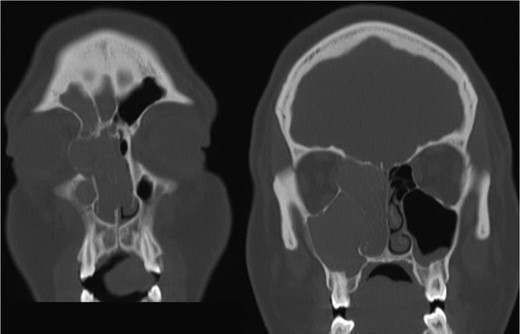

The results of the CT indicated complete opacification of the frontal, ethmoidal, sphenoidal and maxillary sinus on the right side with hyper-dense intraluminal soft tissue filling the sinus cavities. Significant widening of the ostiomeatal complex was observed (Fig. 1). Soft tissue from the right maxillary sinus extended into the right side of the nasal cavity. Extensive changes in the right ethmoidal labyrinth were also discovered. The intact lamella of the middle turbinate and lamella of the bulla ethmoidalis extended further laterally when compared to the left side, and lamina papyracea was protruding into the orbit (Figs 1 and 2). Options were discussed and endoscopic CT guided surgery was recommended.

Coronal CT image indicating extent of soft tissue in the right nasal passage, malformation of the right lamina papyracea, and complete opacification of the right maxillary, ethmoidal and frontal sinus.